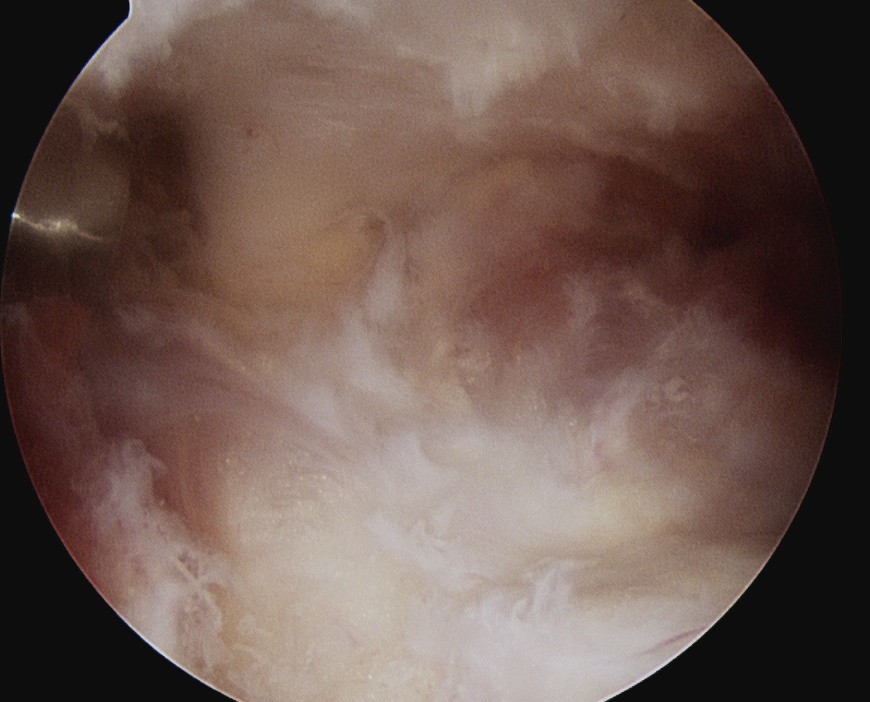

Subacromial space approach

Ghodadra et al Arthroscopy 2009

- subacromial space

- identify spine of scapula and dissect between infraspinatous and supraspinatous

- accessory posterior portal, retract IS and nerve

- decompress with shaver

Subacromial space approach to cyst decompression